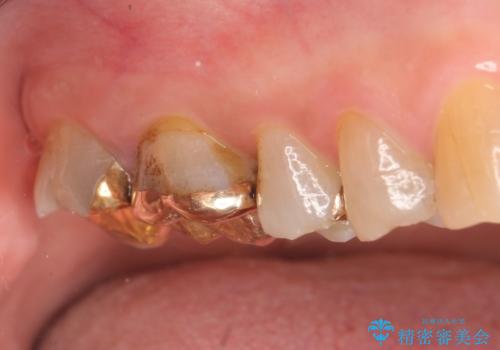

右上6,7の金歯を外したところ、虫歯が歯茎より深い位置まで進行していたため歯周外科を行いました。

その後歯茎の回復を待ち、オールセラミッククラウンおよびセラミックインレーによる補綴・修復を行いました。

そのため当院では歯周外科手術(歯茎を下げる手術)や歯の挺出による、虫歯が歯茎より深いという問題の解決を推奨しております。